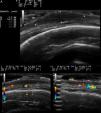

Se realizó una ecografía (sonda 18MHz, eSaote MyLab25Gold) que en modo B mostró un nódulo predominantemente hipoecoico de 3,7mm×16,5mm y bordes bien definidos localizado en la dermis profunda y en el tejido celular subcutáneo (fig. 2A). La periferia de la lesión presentaba una ecogenicidad mixta en contraste con la zona central, más hipoecoica. En la parte inferior se observó una zona hiperecogénica que podría corresponderse con un refuerzo posterior. La epidermis aparecía como una banda hiperecoica. La lesión se extendía en el plano horizontal de forma difusa, siendo más difícil la identificación de sus límites en ese plano (figs. 2B y C). Así mismo, en los bordes laterales de la lesión y en las zonas no nodulares de la neoformación predominaba la ecogenicidad mixta sobre las zonas hipoecoicas. El Doppler color mostraba una neovascularización asimétrica e irregular en la periferia de la lesión (figs. 2B y C).

A. Nódulo hipoecoico de bordes bien definidos donde los bordes son de una ecogenicidad ligeramente superior al centro. B. El doppler color mostraba un aumento de la vascularización y vasos de mediano calibre asimétricamente distribuidos en la base del nódulo. C. Aumento de la vascularización en la zona no nodular de la lesión.